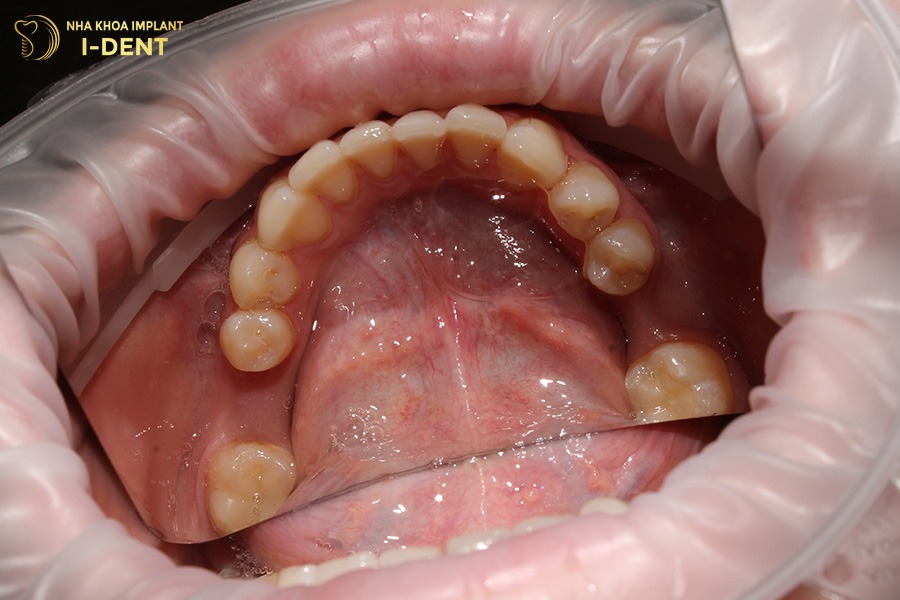

Khi bị rụng răng, bệnh nhân nên phục hình sớm để tránh tiêu xương hàm, xô lệch răng kế cận và khôi phục thẩm mỹ khuôn mặt. Tùy vào tình trạng răng và điều kiện sức khỏe, nha sĩ sẽ tư vấn giải pháp trồng răng phù hợp:

- Trồng răng Implant: Là phương pháp hiện đại nhất, cấy trực tiếp trụ titanium vào xương hàm để thay thế chân răng thật, sau đó gắn mão sứ lên trên. Implant giúp phục hồi gần như hoàn toàn chức năng ăn nhai, ngăn tiêu xương hàm và mang lại cảm giác ăn nhai tự nhiên như răng thật.

- Làm cầu răng sứ: Phù hợp với trường hợp mất 1–2 răng liên tiếp. Phương pháp này mài nhỏ 2 răng kế cận để làm trụ nâng đỡ cho dãy cầu sứ bên trên. Ưu điểm là thời gian thực hiện nhanh, tính thẩm mỹ cao; tuy nhiên cần mài răng thật nên có thể ảnh hưởng đến cấu trúc răng về lâu dài.

- Làm hàm giả tháo lắp: Là lựa chọn kinh tế, thường dùng cho bệnh nhân lớn tuổi hoặc bệnh nhân mất nhiều răng. Hàm được làm từ nhựa hoặc khung kim loại có thể tháo ra vệ sinh dễ dàng. Phương pháp này có ưu điểm là chi phí thấp nhưng hàm tháo lắp không bền chắc, lực nhai yếu và không ngăn được tình trạng tiêu xương hàm.